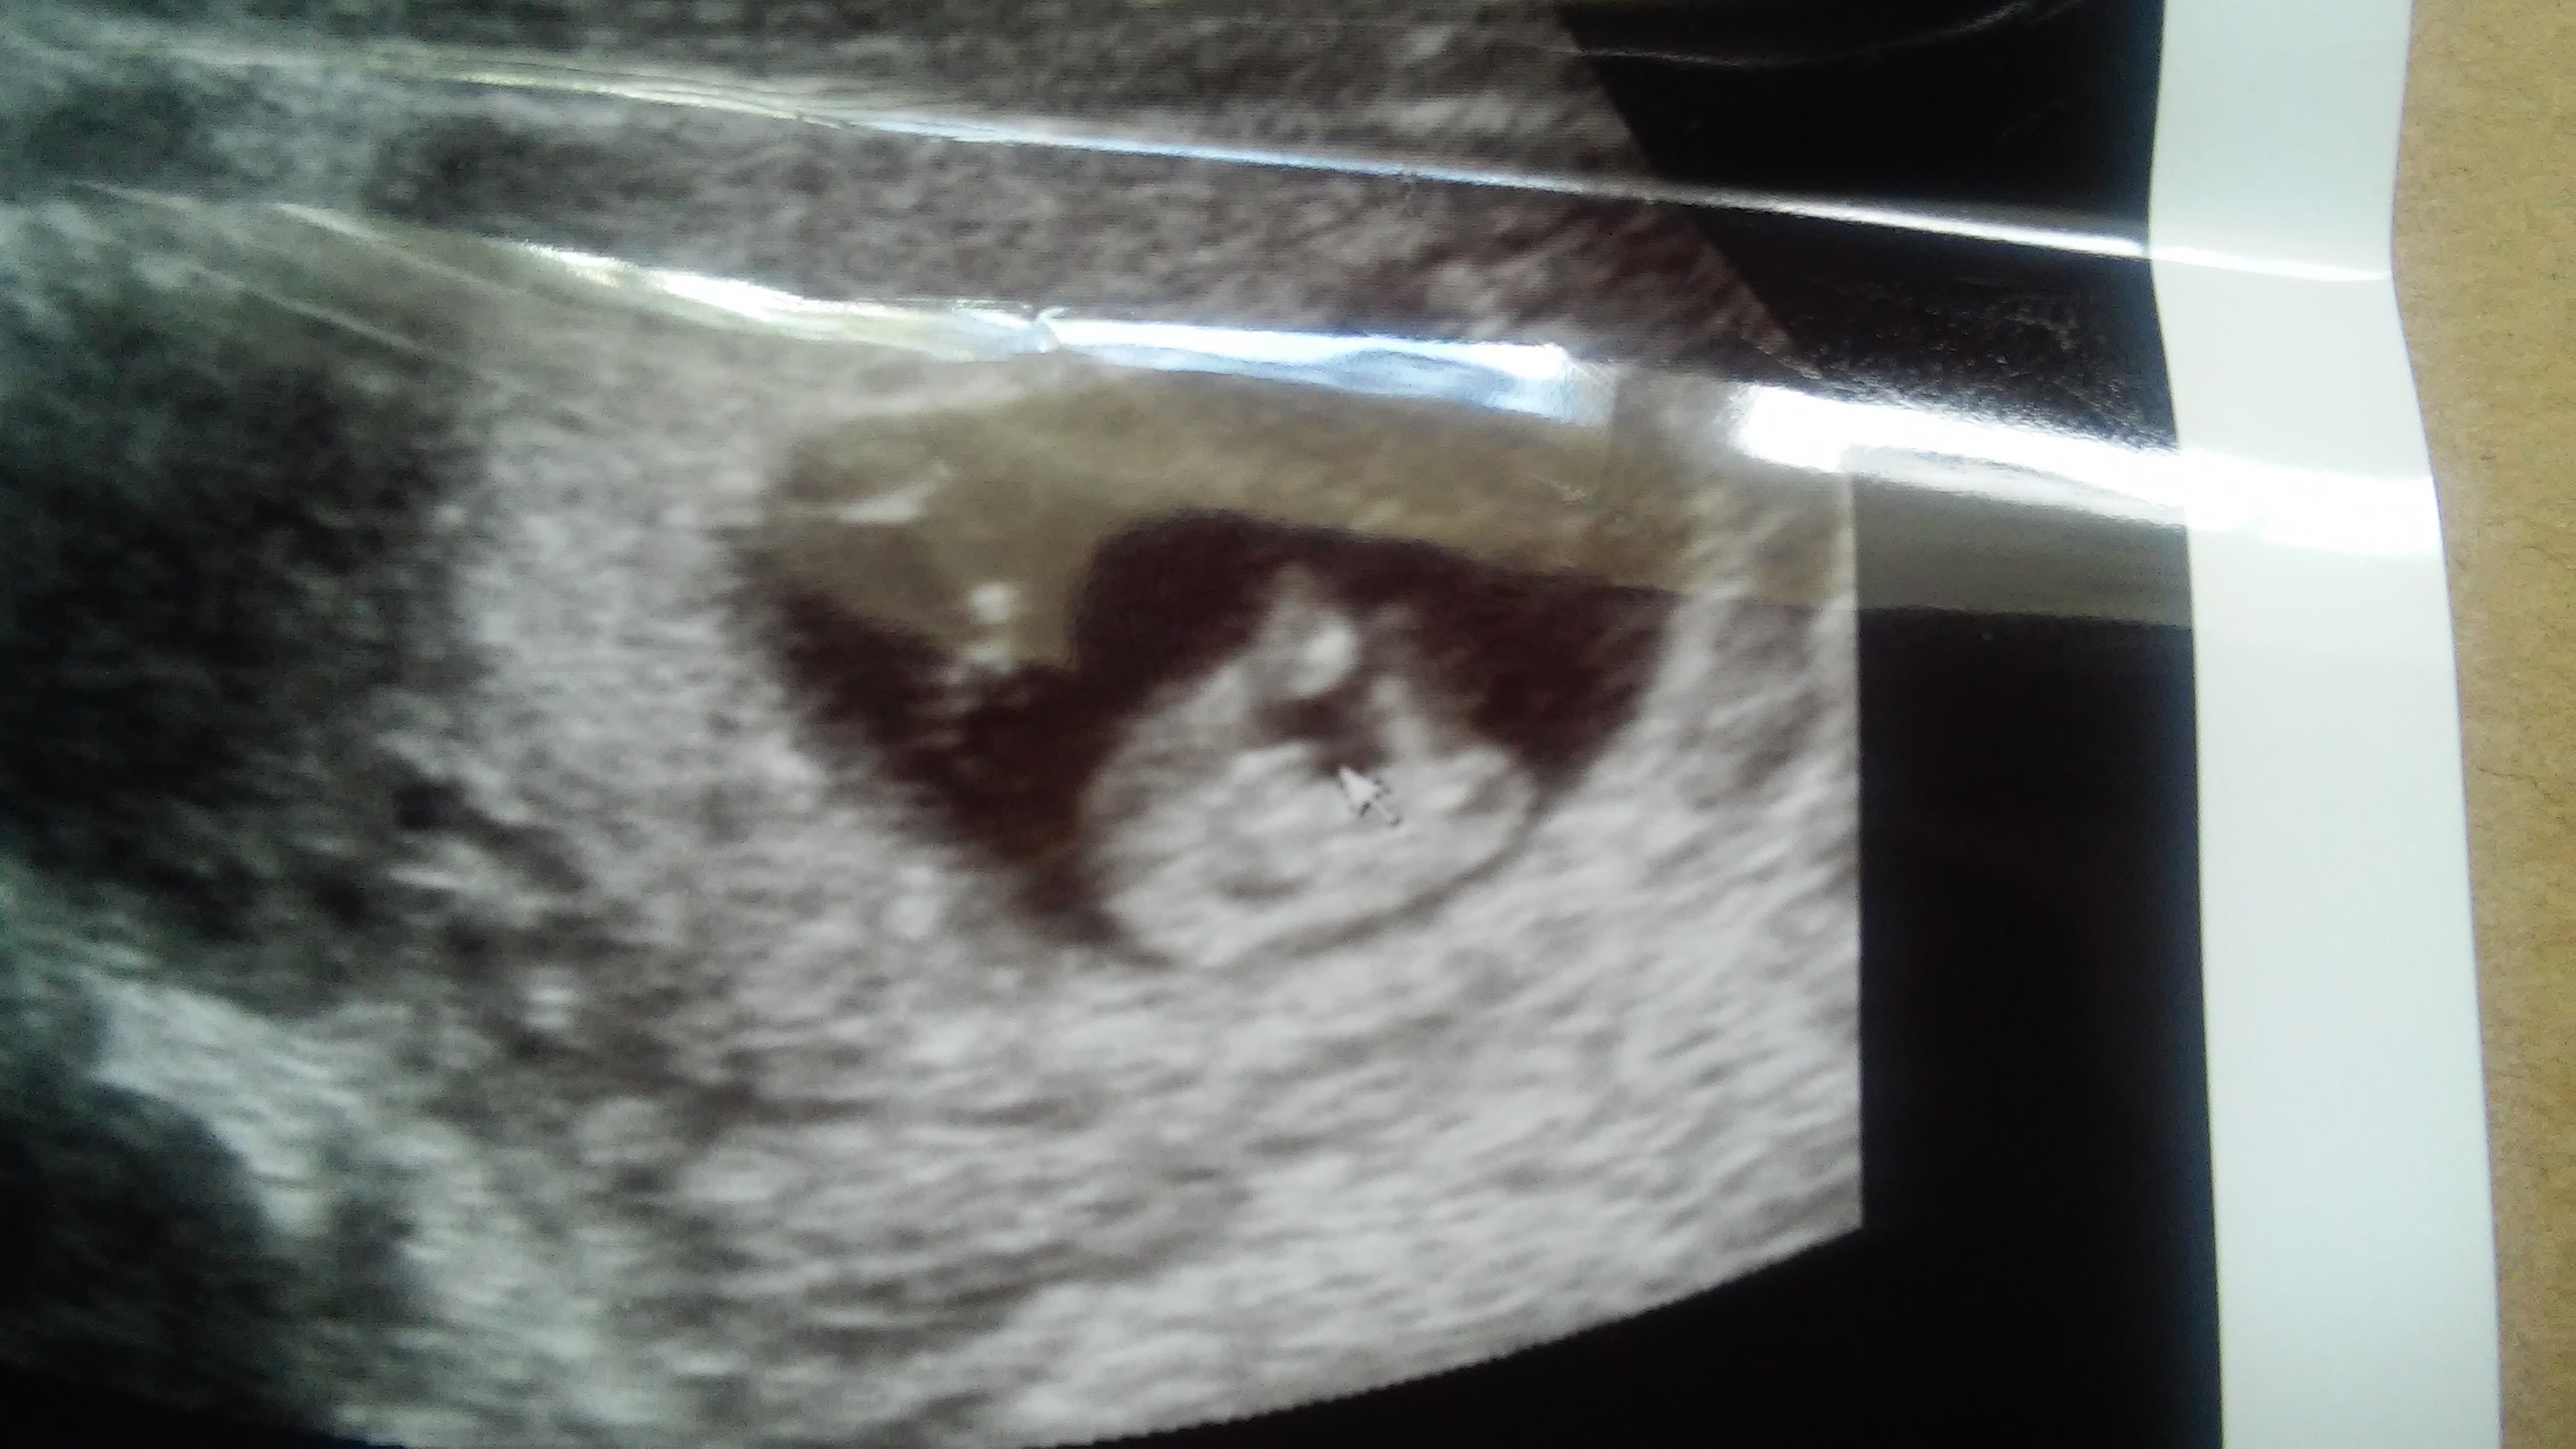

PLEASE help guessing gender.. boy or girl??? 12wks

Im am dying to know what i will have a boy or a girl! im 12 weeks and 2 days and had an ultrasound done today. PLEASE NOTE the umbilical cord was basically in the way the whole time thats the huge white thing in between the legs lol, so dont mistake that for something else :-)im hoping someone is able to look past the cord!! the ultra sound lady did gave me a picture of the butt, she placed an arrow next to it. they didnt want to give me a guess on the gender because theyre not allowed to with 12 weeks...

please help me figuring this out!! thank you so much!!Attachment 25235 Attachment 25236 Attachment 25237